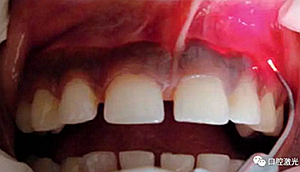

患者22歲,女性,主訴牙齦發(fā)黑??谇粰z查顯示牙齦部位呈黑色,但軟組織健康,沒有表皮粗糙或水腫現(xiàn)象。計(jì)劃使用半導(dǎo)體激光進(jìn)行治療。手術(shù)前患者無需表麻或局麻。采用光纖接觸方式,激光功率設(shè)定為1.5W至2W,連續(xù)模式。氣化黑色牙齦區(qū)域上皮組織。不斷重復(fù)該過程,直至足夠深度的牙齦軟組織表皮被去除干凈?;颊咝g(shù)后需采用漱口水進(jìn)行口腔護(hù)理。

術(shù)前

術(shù)中